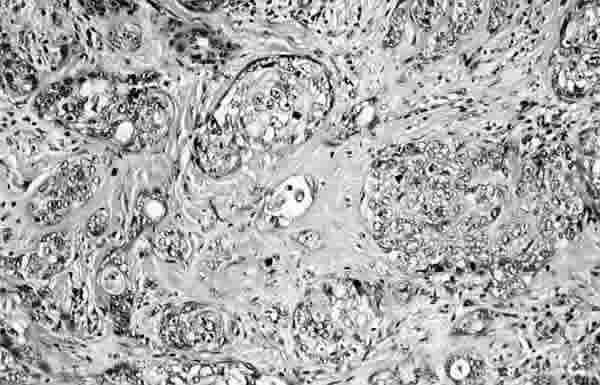

Figura 2

PROLIFERACIÓN DE CÉLULAS DE ASPECTO SEBÁCEO QUE SE DISPONEN EN NIDOS SÓLIDOS. LAS CÉLULAS MUESTRA CITOPLASMAS AMPLIOS, CLAROS Y FINALMENTE VACUOLADOS CON NÚCLEOS HIPERCROMÁTICOS, CON MARCADA ATIPIO Y PRESENCIA DE NUCLEOLOS PROMINENTES (HEMATOXILINA-EOSINA).